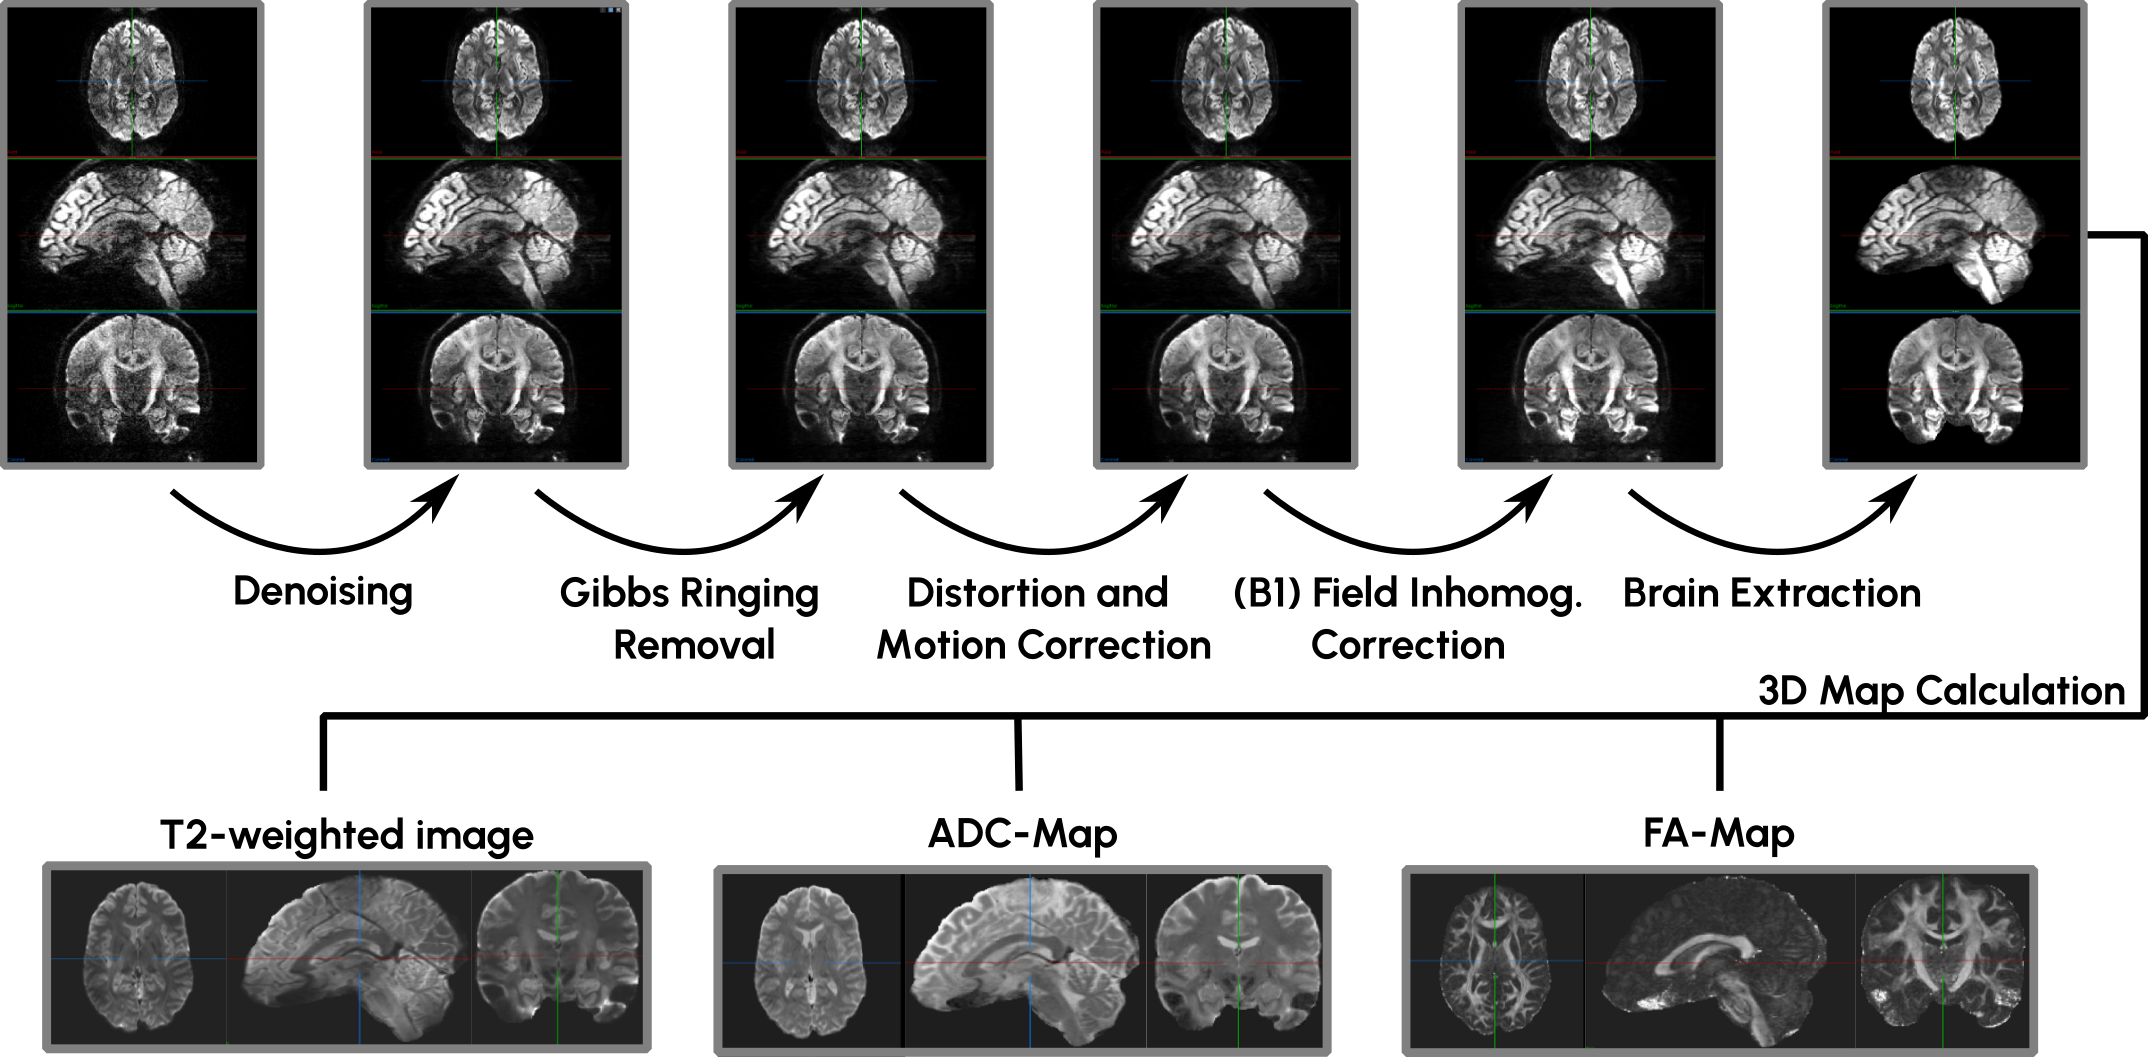

Appendix A DWI Preprocessing

Diffusion-weighted imaging (DWI) measures the diffusion of water molecules in tissue across 3D space. The direction of this diffusion process can be influenced by applying additional magnetic field gradients, allowing researchers to identify tissues that are more or less permeable to water diffusion in specific directions. Because the diffusion process is directionally dependent, multiple images are acquired using gradients of varying strengths to, for example, quantify anisotropies in diffusion behavior. As a result, DWIs are typically composed of a stack of 3D images, forming complex 4D images that are challenging to process and integrate.

To manage the complexity of these 4D images, they are preprocessed into more manageable single 3D image formats that describe specific properties derived from the diffusion measurements in a more interpretable manner. These 3D derivatives of the DWIs allow easier integration into standard SSL pipelines. Specifically, we create T2-weighted, ADC, and FA maps from the original 4D DWI stacks.

Refer to caption

Figure 3: DWI preprocessing pipeline: To derive 3D images from the 4D DWI images, they are processed through six steps, denoising, ringing removal, co-registration, field correction, brain extraction, and lastly 3D derivative creation. Best viewed on a screen to see the differences between steps.

The overall preprocessing pipeline is composed of six steps, displayed in Figure 3: i) Denoising of each 3D image. ii) Gibbs ringing artifact removal of each 3D image. iii) Co-registration of all images to one reference image to correct for potential distortions and motion artifacts. iv) Field correction of potential B1 field inhomogeneities. v) Brain extraction to remove skull and potentially existing face tissue that is not accounted for in the Map creation. vi) Actual creation of the 3D derivates, namely a T2-weighted image, an ADC-Map and an FA-Map.